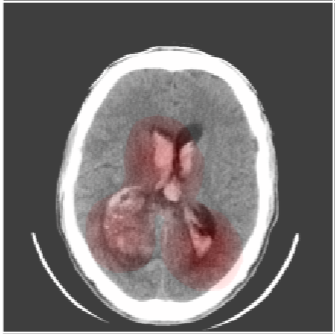

Inverse Problems in Neuroscience: Susceptibility Tensor Imaging

Inverse Problems in Radiology